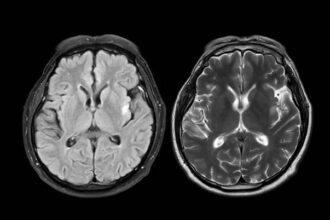

Think you know what’s inside your head? Think again. Scientists have just completed something that sounds like science fiction: a complete cellular map of an entire mammalian brain. We’re talking about every single one of the 32 million cells that make up a mouse brain, cataloged down to their exact location, type, and molecular fingerprint.

This isn’t just impressive—it’s revolutionary. For the first time in human history, we can peer inside the brain’s most intricate networks with unprecedented clarity. The mouse brain, which serves as our primary model for understanding human neuroscience, has been dissected cell by cell, revealing secrets that could unlock treatments for everything from depression to Alzheimer’s disease.

Here’s what makes this breakthrough so significant: researchers didn’t just count cells—they created a hierarchical blueprint showing exactly how brain circuits operate. The atlas reveals which cells talk to which other cells, what chemical languages they use, and how they’re organized into the complex networks that somehow generate consciousness, memory, and thought.